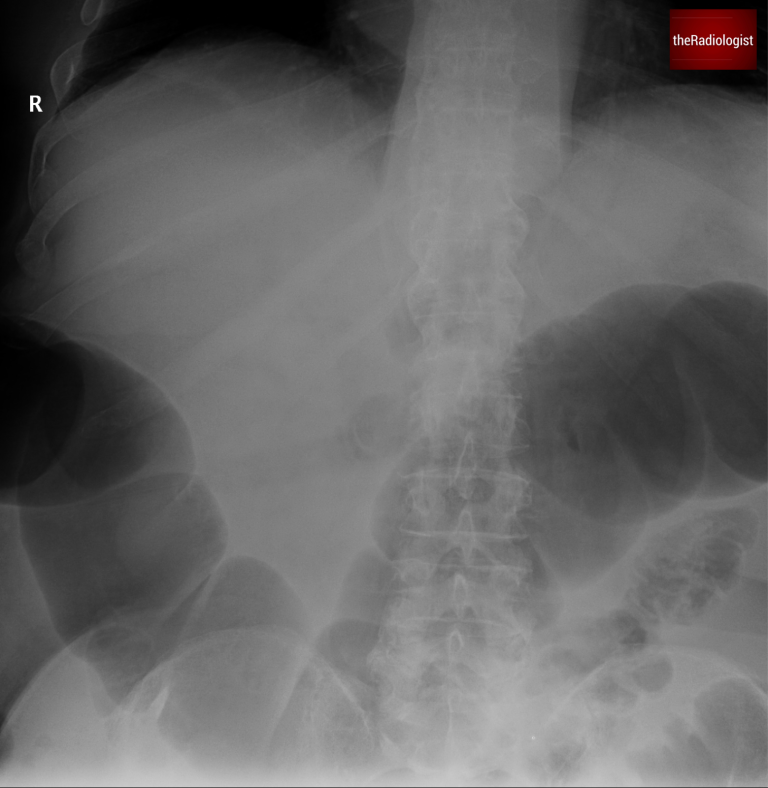

A female in her 60s presents with lower abdominal pain and absolute constipation. Here is her abdominal X-Ray (two separate images):

Abdominal X-Ray on presentation: image 1

This abdominal X-Ray a difficult film to assess as it is split into two but we can see dilated bowel loops. Let’s have a look at this table below which helps us differentiate between large and small bowel obstruction.

In this case instead of valvulae conniventes traversing the whole wall of the bowel which we with small bowel, we can see haustrae which we can just see at the periphery of the bowel lumen. This along with the degree of distension points us towards mechanical large bowel obstruction.

We can see haustrae which do not traverse the whole bowel wall rather than valvulae conniventes within small bowel which do – this points to large bowel dilatation.